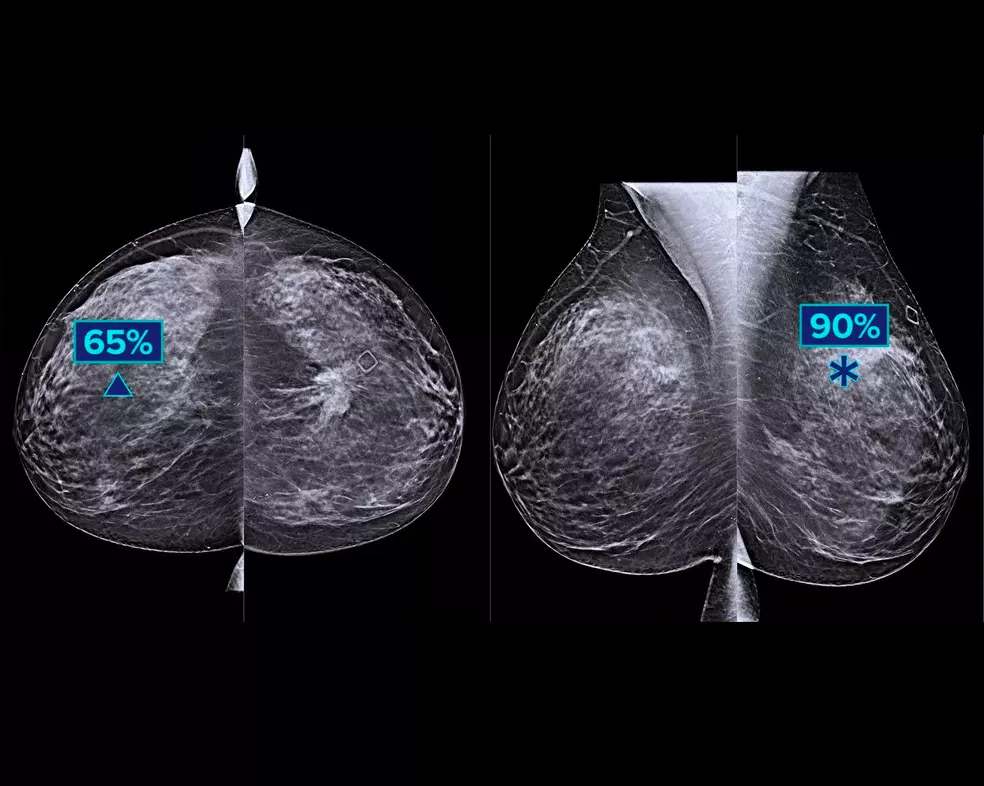

Genius AI™ Detection ist ein Deep-Learning-Algorithmus, der Radiologen bei der Diagnose unterstützt und Brustkrebs auf Tomosynthesebildern erkennt 1-3 , die mit Hologic Dimensions Mammography® Systemen aufgenommen wurden. Der Algorithmus lokalisiert Läsionen, die wie Brustkrebs aussehen, indem er jedes Schnittbild eines Tomosynthese-Bildsatzes durchsucht. Verdächtige Areale werden auf der Workstation des Radiologen zur einfacheren Befundung gekennzeichnet.

Der Algorithmus sucht nach 3 Hauptgruppen verdächtiger Läsionen: Verkalkungen, Raumforderungen, Verdichtungen und anormale Strukturen sowie Kombinationen dieser Läsionen. Die Ergebnisse können je nach Befundungsworkstation variieren.